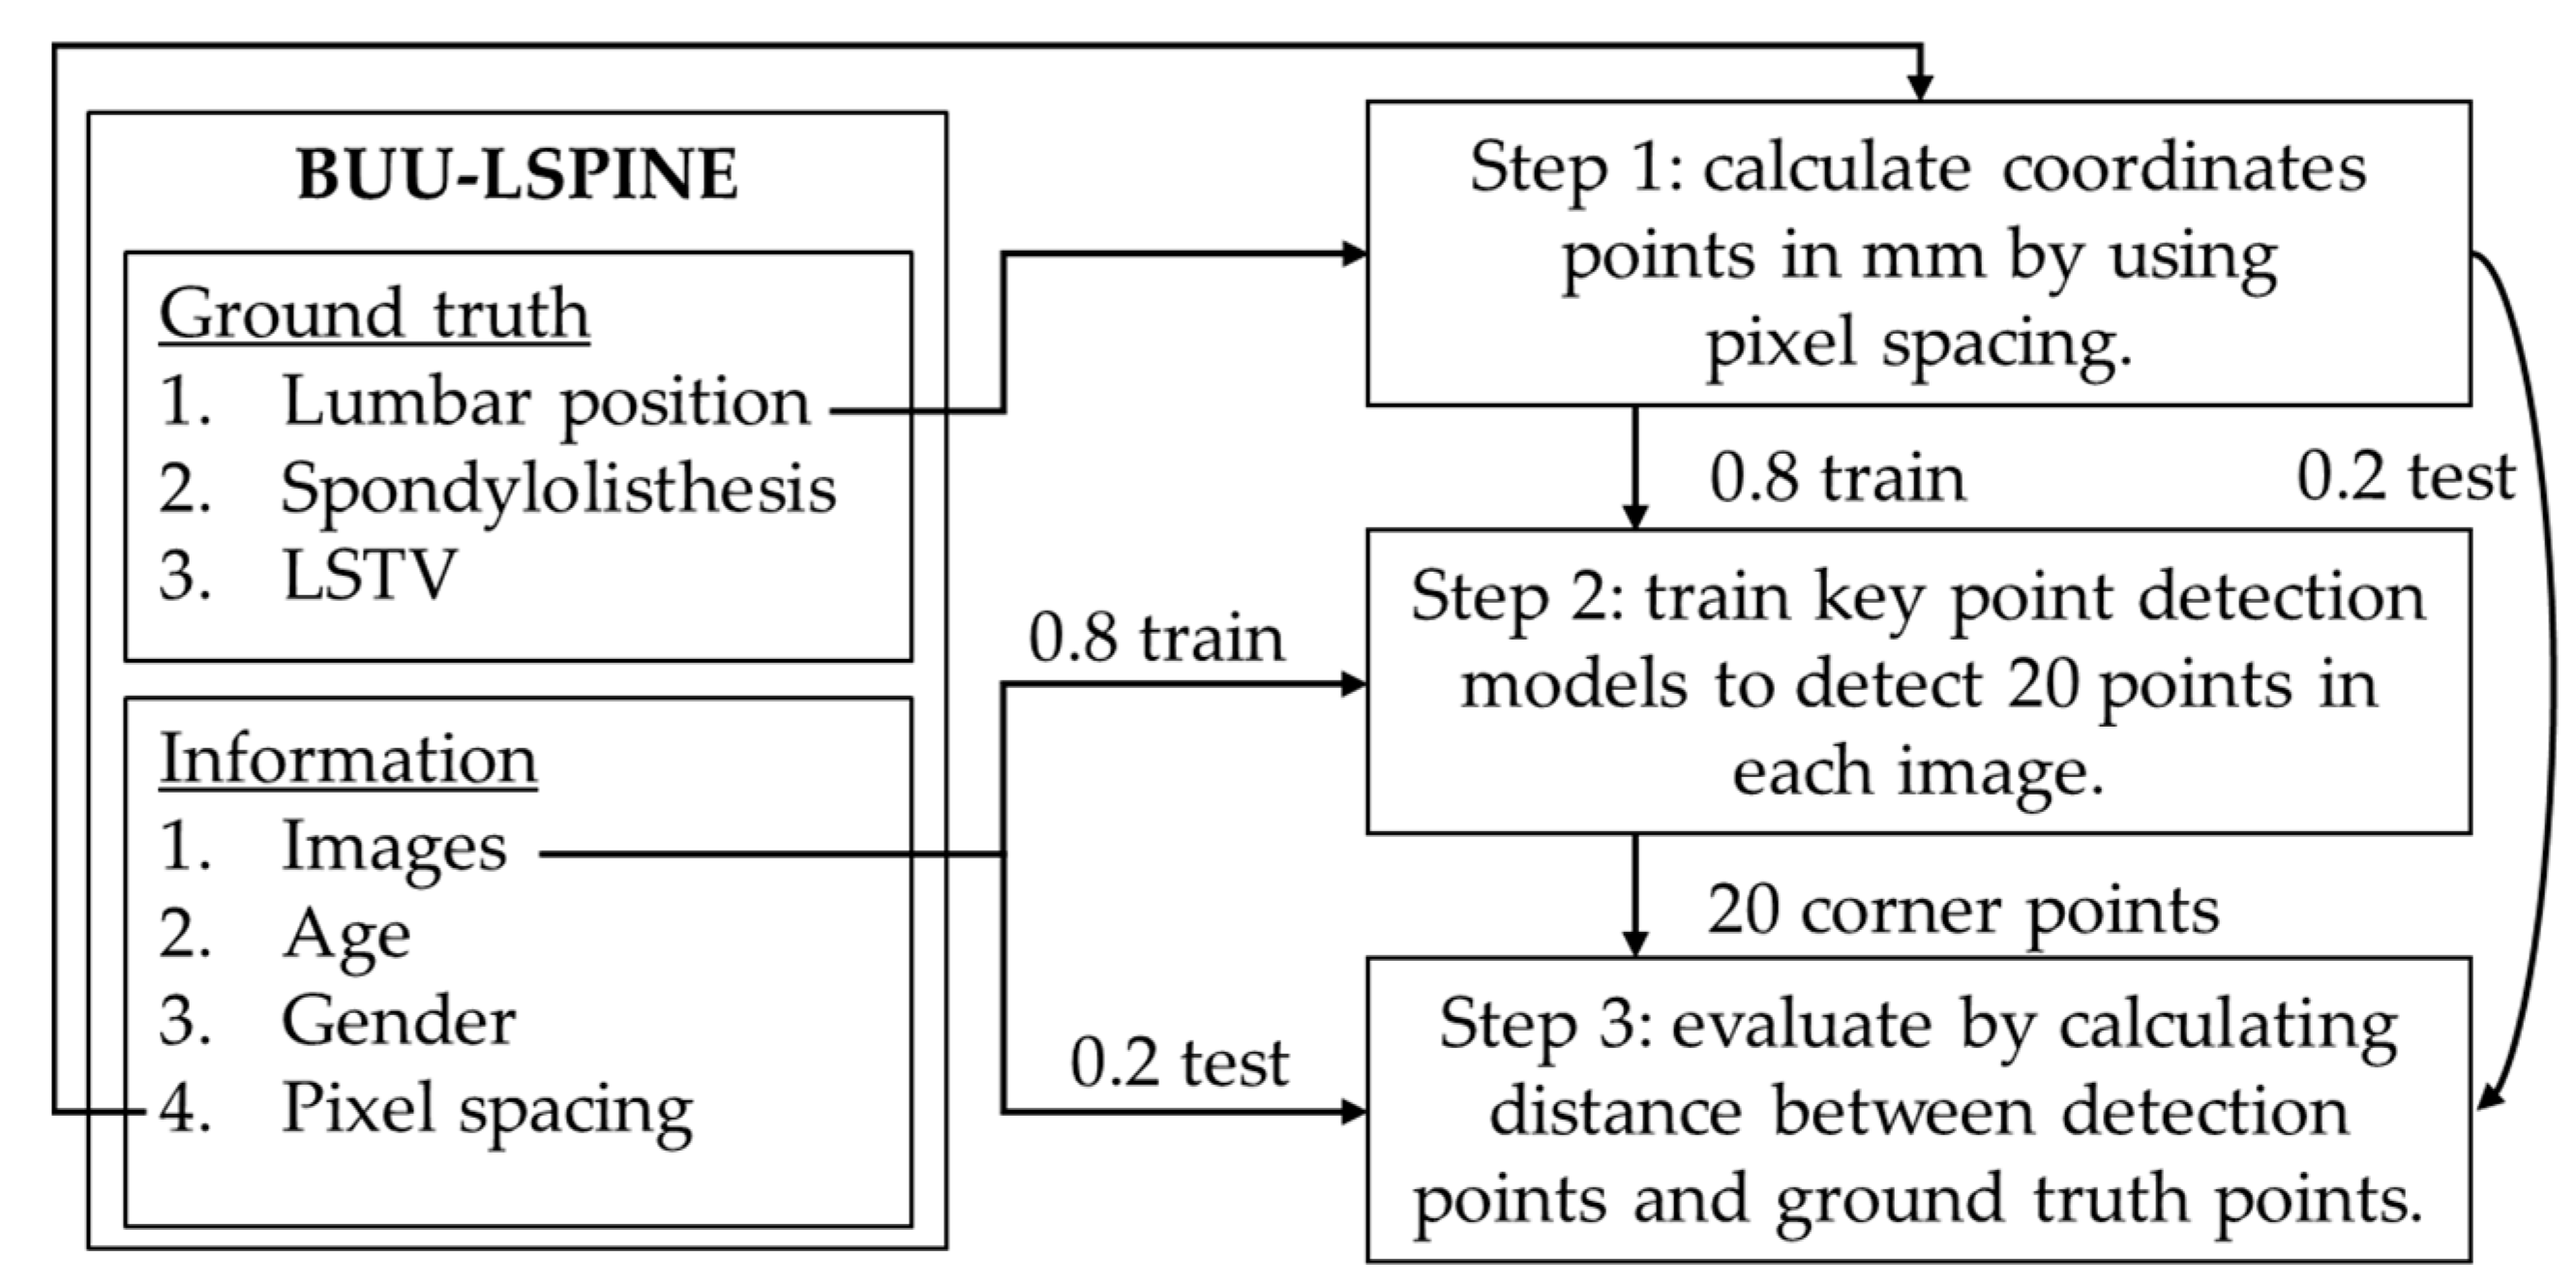

2.4.2. Vertebral Corner Points Extraction

3.2. Vertebral Corner Point Extraction